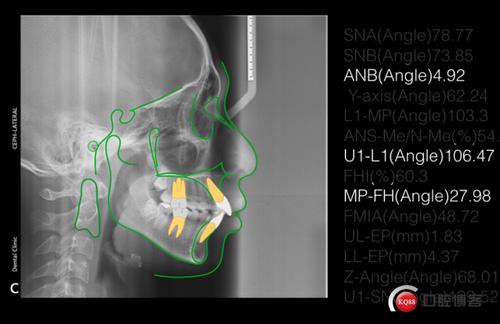

8个月拔牙矫正双颌前突